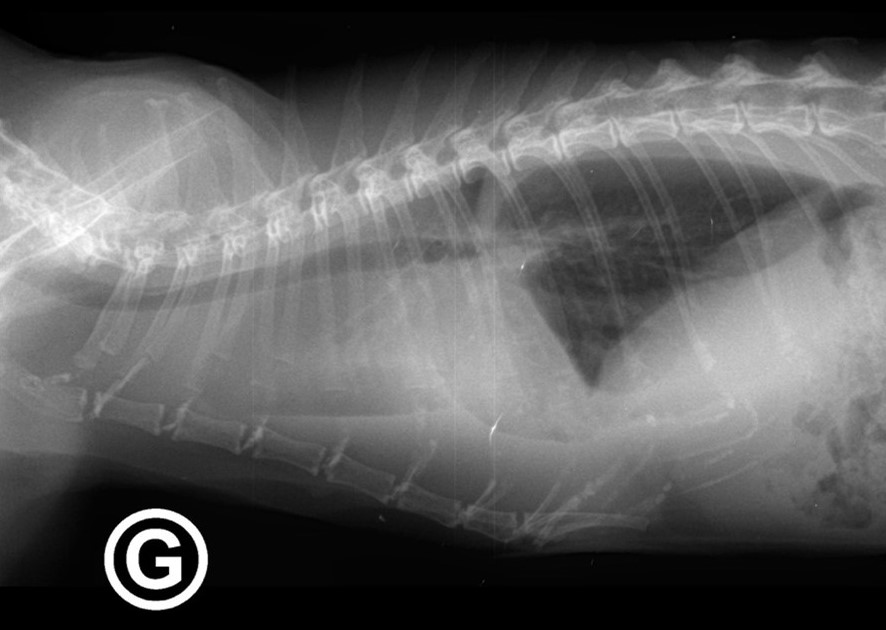

Épanchement pleural (liquide dans le thorax) d’un chat